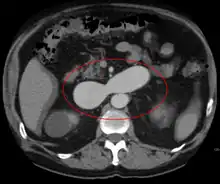

AVMs can occur in various parts of the body:

- brain (cerebral AV malformation)

- spleen[13]

- lung[14][15]

- kidney[16]

- spinal cord[17]

- liver[18]

- intercostal space[19]

- iris[20]

- spermatic cord[21]

- extremities – arm, shoulder, etc.